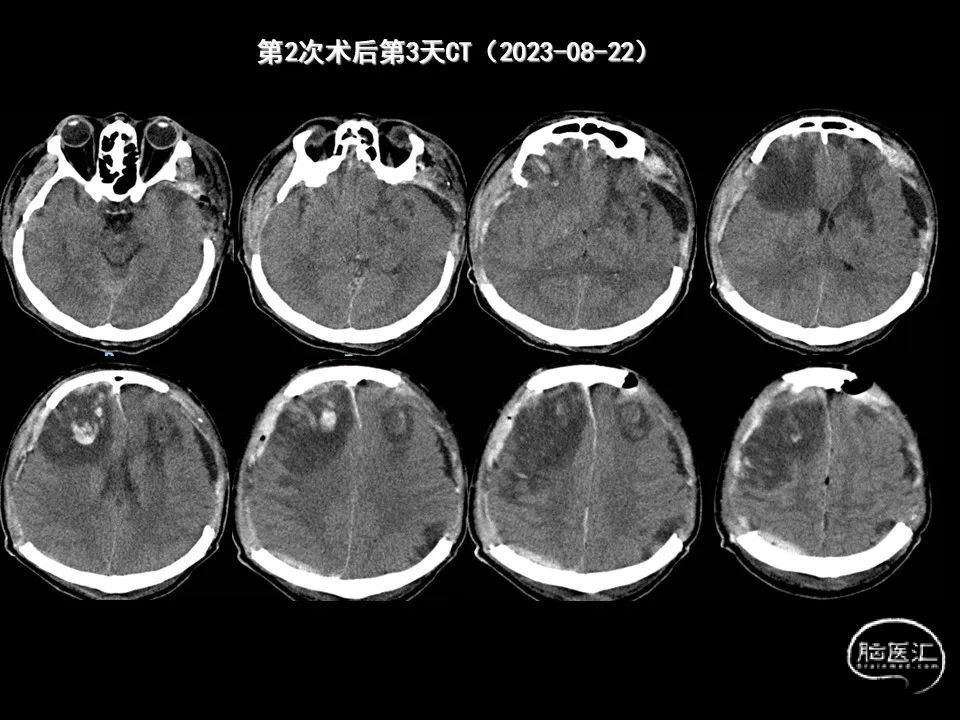

今天为大家分享的是《监测有道丨颅脑创伤-神经重症周刊》第338期,由海南省人民医院朱蔚林教授带来的:2例脑出血微创手术,欢迎阅读、分享。